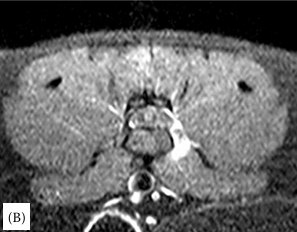

연구 대상은 4세 장모 고양이로 갑작스러운 좌측 후지 절뚝거림과 점프 회피 증상을 보였다. MRI 검사 결과, L6–L7 추간판이 원외측으로 탈출해 신경근을 압박하고, 국소 염증을 동반한 사실이 밝혀졌다. 이는 지금까지 개에서만 드물게 보고된 질환으로 고양이에서는 최초 사례다.

치료 과정에서 일반 소염제는 효과가 없었으나 프레드니솔론(스테로이드) 치료를 통해 15일 만에 임상 증상이 완전히 소실되며 성공적인 회복을 보였다. 이는 고양이에서 수술 없이도 보존적치료로 호전될 수 있음을 보여준 중요한 임상적 의미를 가진다.